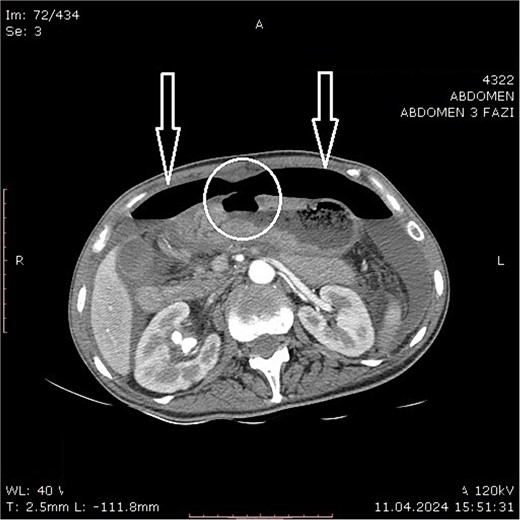

Physical examination revealed clinical signs of an acute abdomen with a rigid abdomen with diffuse abdominal wall tenderness. Laboratory blood analysis, an abdominal computed tomography (CT) scan, and a chest X-ray were performed after admission. The following laboratory findings were abnormal: hemoglobin level of 91.00 g/L (120.00–165.00 g/L); leukocytes count of 23.40 109/L (3.50–10.00 X109/L); neutrophil count of 21.40109/L (1.20–8.00 x109/L); platelets count of 1089.00109/L (150.00–390.00109/L); serum urea value of 9.40 mmol/L (2.10–8.20 mmol/L); total serum protein value of 57.30 g/L (64.00–83.00 g/L); serum albumin level of 30.00 g/L (35.00–50.00 g/L); C reactive protein level of 287.20 mg/L (0.00–5.00 mg/L). A CT scan revealed large air pockets in the abdomen and pneumoperitoneum presence. Free fluid with a density of up to 15 Hounsfield units was observed in all spaces of the abdomen. A defect on the anterior gastric wall was seen (Fig. 1). According to the findings suggestive of a hollow intraabdominal viscus perforation, an emergency laparotomy was undertaken. The calculated risk and predicted survival according to Boey’s score [6] of the patient were 2, with a calculated morbidity risk of 75% and a mortality risk of 33%.

Abdominal computer tomography (axial scan) with pneumoperitoneum (arrows) and visible discontinuity of the anterior stomach wall suggestive of ulcer perforation (encircled).